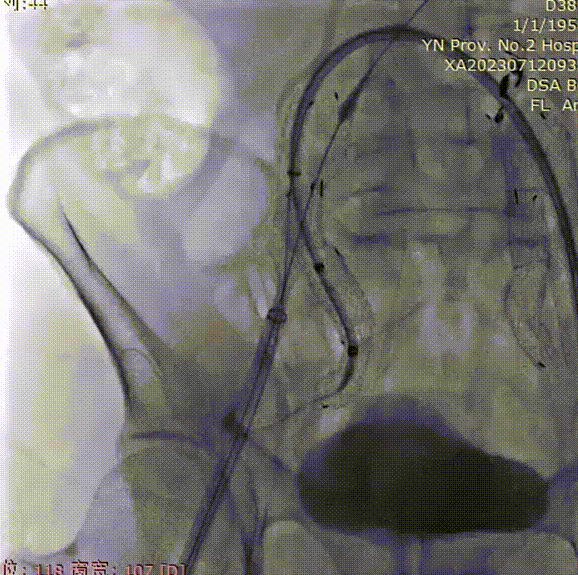

支架植入前造影

双侧股动脉入路,左侧置入18Fr 33cm GORE® DrySeal 亲水涂层导引鞘(以下简称“DSF导引鞘”),右侧置入12Fr 45cm DSF导引鞘;建立翻山通路后将标记猪尾导管头端置于肾动脉开口上方,做腹主动脉造影:显影显示双侧髂总动脉瘤;肾动脉开口到右髂内距离约200mm。